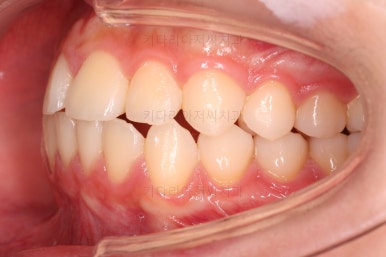

초진 시의 다른 부위들 사진입니다.

약간의 주걱턱 느낌에 약간의 돌출감, 전반적인 치열의 가지런한 느낌은 나쁘진 않았지만 약간의 불량한 교합상태였어요.

다른 부분은 크게 바꾸지 말고 약간의 교합 조절과 어금니 치료에 초점을 맞춰서 교정치료 계획을 잡았습니다.

전후사진을 비교해 볼게요.

약간의 주걱턱, 돌출입은 고칠 의사가 없어서 그대로 유지하였고 주걱턱 패턴으로 인한 부정교합 부분을 개선했으며 무엇보다 중요한 것은 쓰러져서 많이 썩어있던 치아를 자칫 치료 못할 뻔 했는데 교정치료와 병행하여 훌륭하게 치료를 하여 살려 썼다는 점입니다.